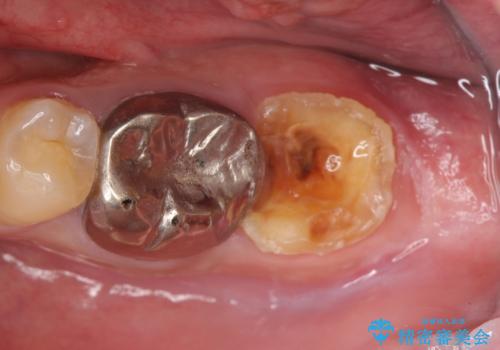

セラミックインレー 下の一番奥歯 歯ぐきの厚みを減らしてぴったりに入れます(ディスタルウェッジ+骨外科)